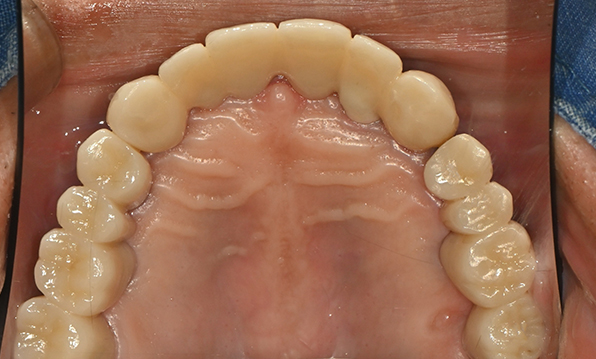

전체 임플란트

위 아래 치아가 정확하게 맞아야하는 고난이도 임플란트

임상 경험이 많은 숙련된 전문의의 섬세한 기술력이 중요합니다.

잇몸뼈 충분히 이식 후 임플란트 식립

성공을 위한 노하우, 잇몸뼈 재건 기술

이 때, 치조골 이식을 병행하여 잇몸뼈 재건 후 안정적인 임플란트 식립을 하고 있습니다.

치료기간 : 2021.04.12~2021.09.15